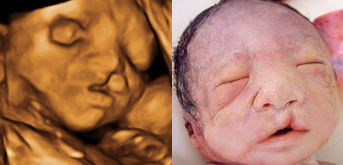

唇裂

嘴横裂